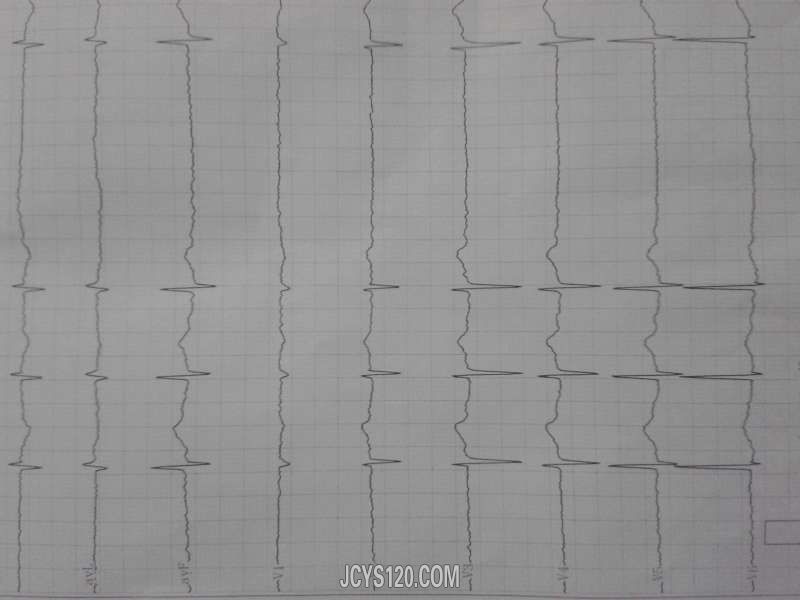

阵发性心悸1年。省级医院做的 24小时动态心电结果如下图

奇怪的是 该患者无症状